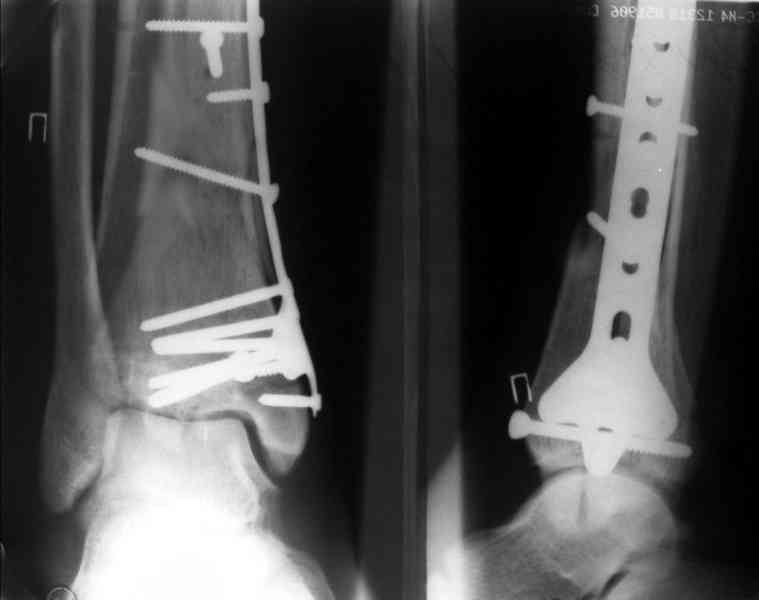

Посылаю результат лечения предыдущего больного через год.

Кстати, при переломах переднего края по классификации АО В-3 при переломах пилона пластина укладывается по передней поверхности. Она достаточно тонкая и эластичная, не надо этого бояться. Посылаю три снимка.